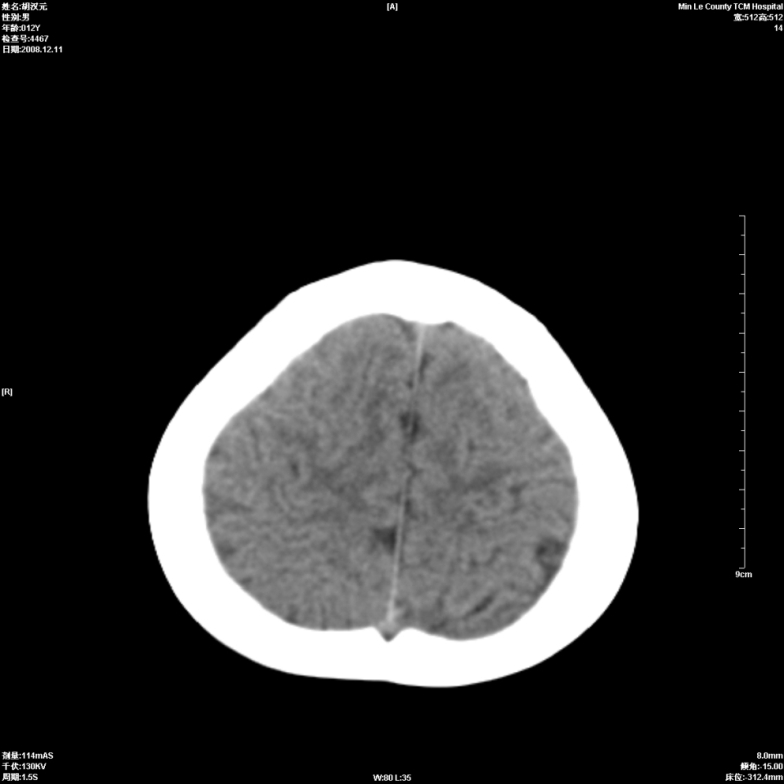

标题: PED1681:头疼发热约一周 [打印本页]

标题: PED1681:头疼发热约一周

颅脑未见确切异常。必要时进一步检查,如mri、脑脊液检查。

两侧顶部近灰质处白质密度降低,是否炎性改变

颅脑ct轴位平扫颅内未见明确异常;建议必要时复查或行进一步检查。

两侧顶部近灰质处白质密度降低,建议mri